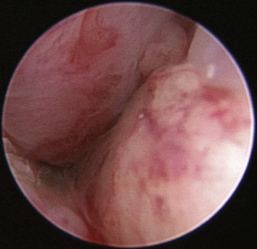

Normal turbinates have a smooth, pink-to-white surface and a spatial alignment that provides channels for the passage of air. The color varies and appears tan in the caudal nasal cavity. Turbinates come in different shapes and sizes, but the surface should be smooth. Ethmoid turbinates in the caudal nasal cavity will have a characteristic stippled or corrugated appearance (Figures 19-13 through 19-16). Ulcerations or various proliferations of the mucosa are indicative of disease. These changes are typically diffuse and accompanied by a lot of mucus. Mucus can be thin to purulent. Copious amounts can be flushed out of the nasal cavity to allow better visibility. The specific disease is determined by biopsy. After full examination of the nasal cavity, run the scope along the floor of the nasal sinus to the level of the choanae. Keeping the scope pointed in a ventral medial direction prevents inadvertent trauma or penetration of the cribriform plate. The index finger of the free hand can be used to follow the scope as it moves caudally over the hard palate; the surgeon can then palpate the scope through the soft palate when it moves into the nasopharynx. Some force is needed to complete this procedure and may result in increased bleeding.

image

Figure 19-13 Normal canine rostral nasal cavity; the septum is medial (left).

Figure 19-14 Normal canine meatus division.

Figure 19-15 Normal canine nasal turbinate mucosa.

Figure 19-16 Normal canine ethmoid turbinate.